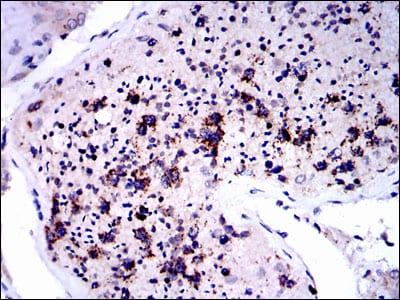

- Immunohistochemical analysis of paraffin-embedded human testis tissues using NQO1 mouse mAb with DAB staining.

- Immunohistochemical analysis of paraffin-embedded human ovarian cancer tissues using NQO1 mouse mAb with DAB staining.